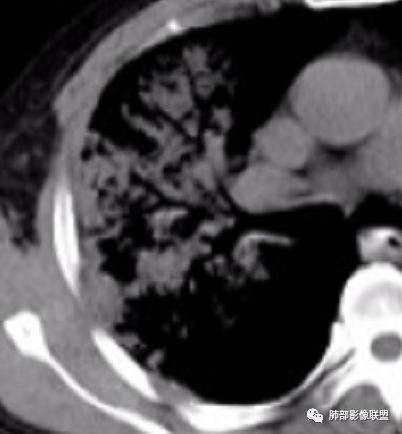

张延军: 克雷白。空洞,叶间裂下坠

青藤之凉: 肺炎克雷伯菌,大家都对了。

肺炎克雷伯菌有局限性,因为痰液粘稠,会造成叶间裂膨出。肺内可能会有蜂窝样改变。有糖尿病、吸烟、支气管病病史者,容易感染肺炎克雷伯菌。可能会有空洞形成,右肺上叶发病最常见。